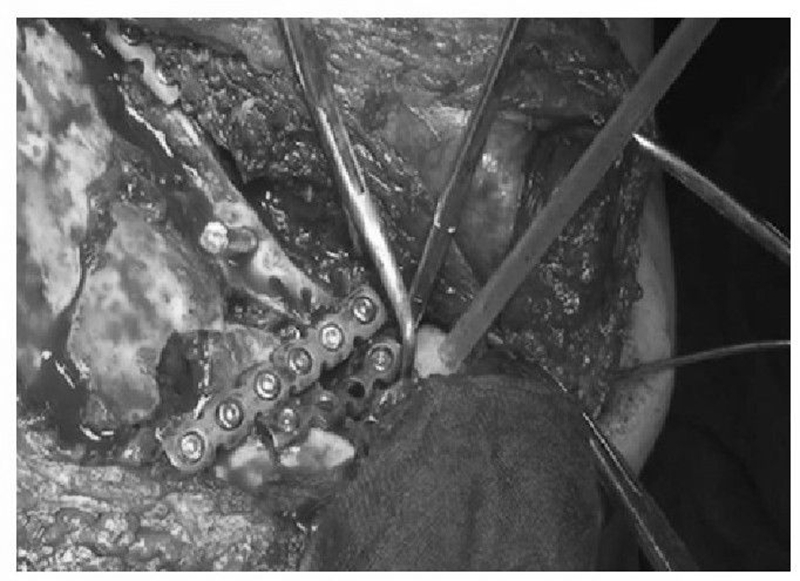

术前设计采用跨骨折区域钢板螺钉固定(图13)。术中可见纵向骨折区域骨质薄弱,骨折粉碎严重,钢板放置位置有限,操作极其困难(图14)。术中采用多块接骨板跨骨折区域固定,术后X线片及三维CT重建显示复位满意(图15)。针对此病例,如果采用缝线辅助固定技术,可使手术操作过程简化,达到同样的固定效果(图16)。

图14 术中示肩胛骨板钉固定

图15 术后X线片及CT三维重建示骨折复位满意,内固定位置良好 图A:术后X线片;图B:术后CT三维重建